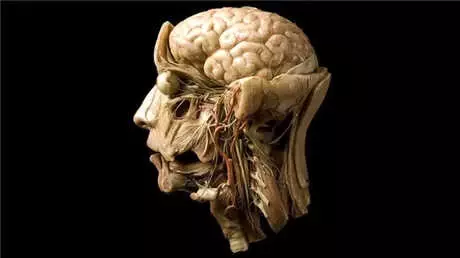

İnsan hipokampusu denizatına oldukça benzer bir yapıdadır:

Beynimizin sağ ve sol ana loblarına uzanan iki kuyruksu yapıdan oluşan hipokampus, insan beynine yandan bakıldığında bir denizatını andırır. Bu şekliyle uzun süre bilim dışı konularda bile tartışma yaratmıştır.